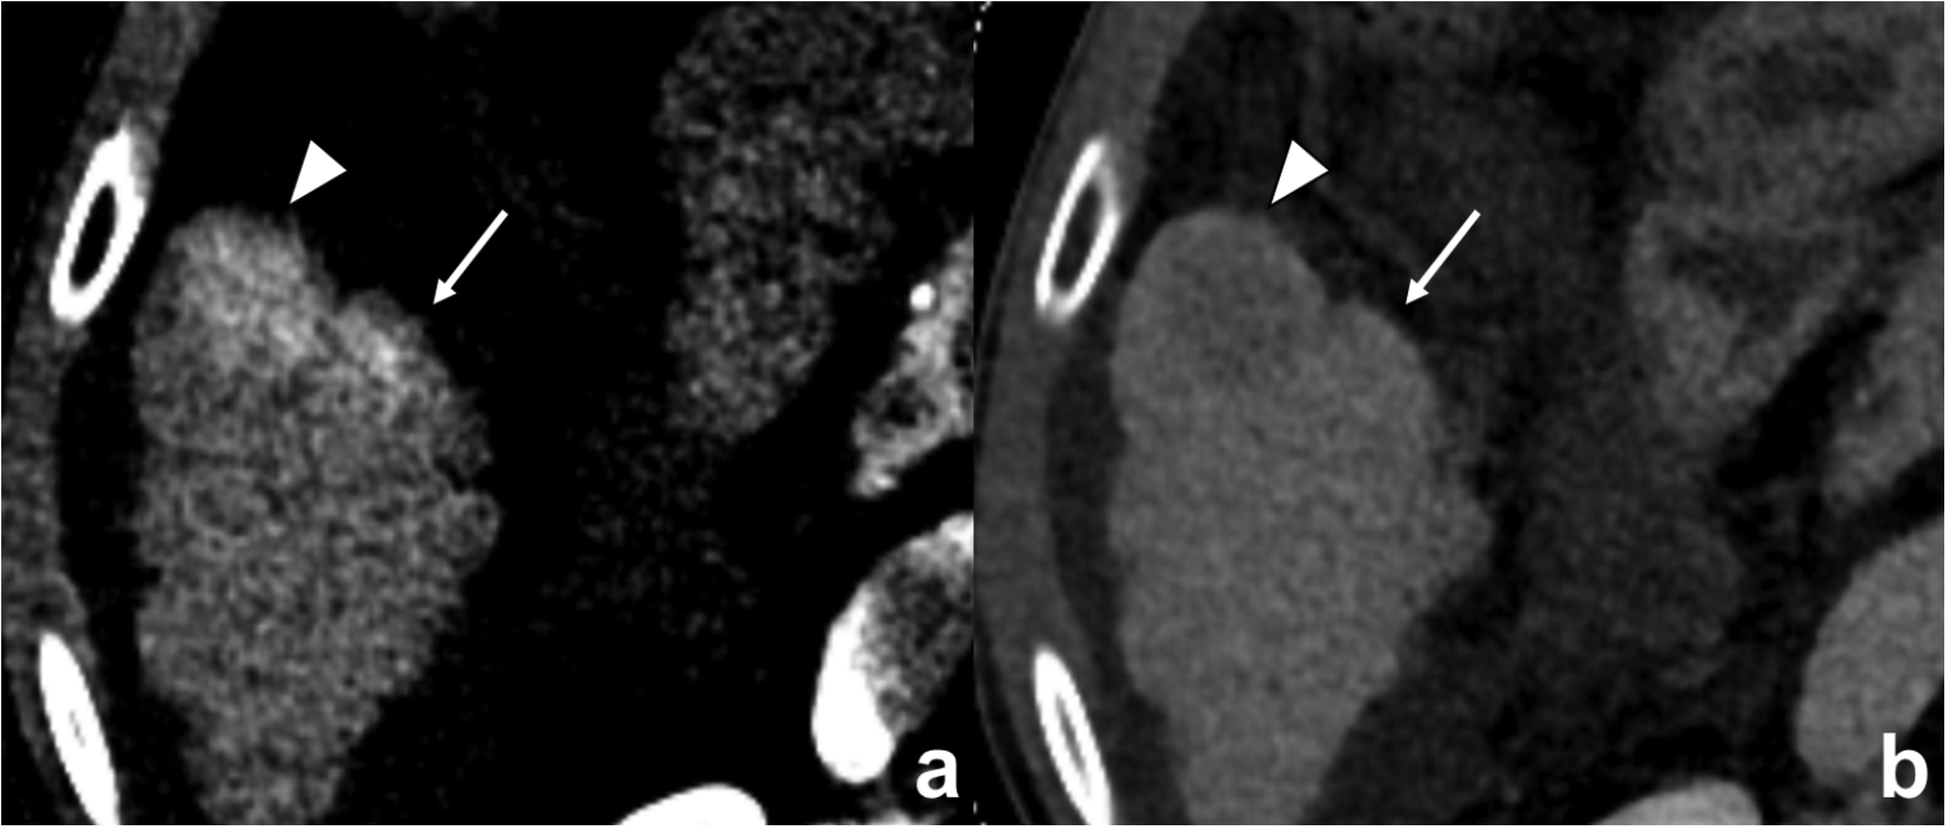

Fig. 5

A 64-year-old man with hepatocellular carcinoma (HCC) without microvascular invasion (MVI). a Enhancing area found in the peritumoral area (arrows) adjacent to the HCC (arrowheads) in the arterial phase, which became b isoattenuation in the equilibrium phase. However, the NIC of the peritumoral layer with a 2-mm distance from the tumor margin is 0.03 mg/mL, lower than 0.082 mg/mL, which is the cutoff value for identifying MVI